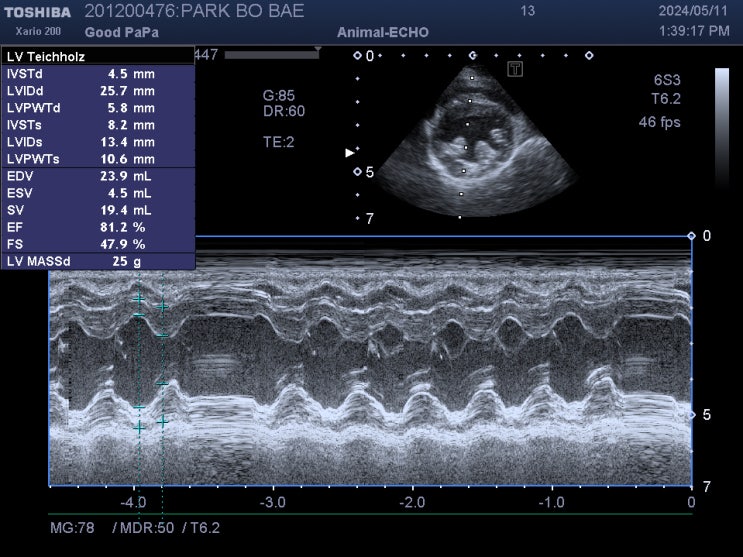

15살 강아지 심장병 폐수종 치료 후기 / 과거에 심장사상충 치료한 노령견 심장병 관리 / 반려견 폐수종 증상, 치료 전문 동물병원 / 강아지 호흡곤란, 호흡이상, 호흡수 증가

안녕하세요~ 굿파파 수의사입니다. 오늘은 근로자의 날이네요~ 번개가 치고, 비가 내리기 시작하네요 따뜻...

15살 푸들 강아지 심장병 & 만성 신부전 관리 1 년 후기 / 노령견 만성신부전증 증상, 치료, 관리법 / 반려견 심장병 관리 전문 동물병원 / 애완견 심장병 증상, 치료 전문

안녕하세요~ 굿파파 수의사입니다. 오늘부터 날씨가 더워지고 수요일에는 여름 날씨가 느껴진다고 합니다. ...